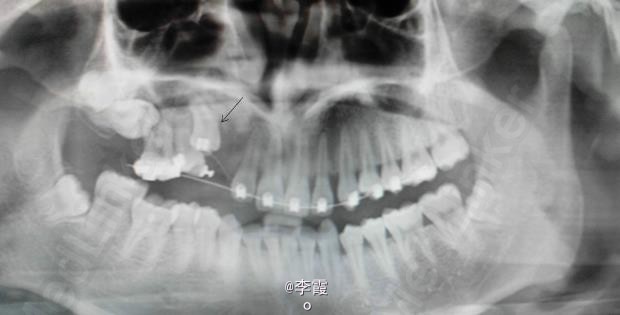

诊断:(1)13含牙囊肿(2)14高位垂直阻生。(3)17高位水平阻生。处理:(1)建议手术拔除15及去除13牙冠周围牙囊,保留13。(2)半年后做13和15正畸牵引。17暂时不做处理。

效果良好,患者满意。